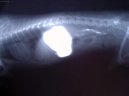

Psí plemena:  > Léčba interních onemocnění (Veterinární zákroky) Léčba interních onemocnění (Veterinární zákroky) - V mnoha případech je nezbytné dlouhodobé podávání antibiotik k zabránění růstu patologické bakteriální mikroflóry ve střevech a aplikace vitamínů.